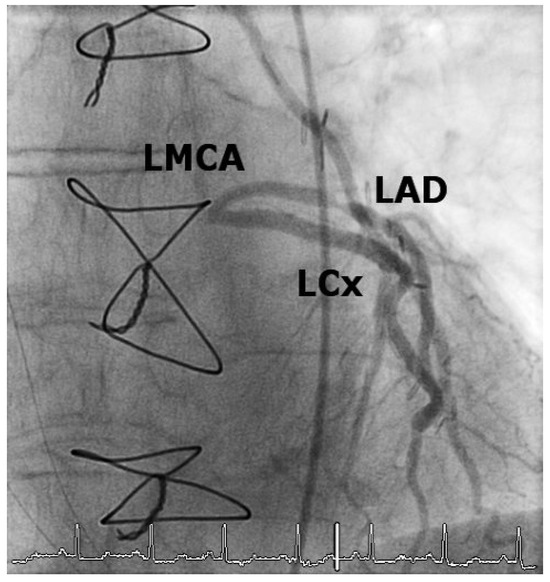

Case2